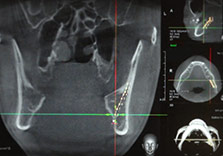

Navigation мэт байрлалыг нарийвчлалтай зааж өгөн,

найдвартай аюулгүй мэс заслын систем

Эмчийн мэдрэмж таамаглалаар хийгддэг ба мэс заслын явцад мэдрэлийн судал гэмтээх магадалалтай Аюулгүй Мэс засалын багаж мэдрэлийн судалруу ойртох төдийд л анхааруулга дугаран мэдрэлийн шугам хөндөх нь 0%

Мэс заслын өмнө урьдчилан дизайн гаргасны дагуу эмчийн туршлагад тулгуурлан хийгддаг байсан ба зөрүү гарах магадлал өндөр Найдвартай Мэс заслын явцад урьдчилсан гаргасан зүсэлт хийх хэсгээр ямар ч зөрүүгүй дэлгэцээр хянагдан хийгдэнэ

Мэс заслын өмнө 2D - ээр ясны хөдөлгөх хэмжээг урьчилан харуулна Үр дүн

3D моделоор мэс заслын өмнөх болон дараах үр дүнг урьдчилан харуулж сэтгэл ханамж өндөр мэс заслын үр дүн

Анхааруулгын тусламжтайгаар ясны зүсэлтийг аюулгүйгээр

Мэс заслын явцад ясны дотуур байрлах мэдрэлийн судал болон шүдний ёзоорын хэсгийг

шалгах боломжгүй учраас. Харин id Navigation эрүүний гажиг засах мэс засал хол зүсэлт х

ийгдэхээр зогсохгүй гүн харан мэс засал хийгдэнэ.

Мэс заслын өмнөх шинжилгээ болон эмчийн туршлагад тулгуурлвал 100% аюулгүй байх боломжгүй. Харин Navigation эрүүний гажиг засах мэс засал нь мэс заслын явцад мэдрэлийн судал болон шүдний ёзоорын хэсгийг шалган анхааруулга дугаран аюулгүй мэс засал хийгдэх боломжтой.

Өнөөг хүртэл зүсэлт хийх хэсгийг эмчийн туршлага ур чадварт бүрэн даатгадаг байсан. Тиймээс алдаа зөрүү байхгүй байх боломжгүй. Navigation эрүүний гажиг засах мэс засал нь мэс заслын явцыг урьдчилан төлөвлөсөний дагуу хийгдэж буйг дэлгэцээр хянан! 1мм-ийн ч зөрүүгүй! мэс засал хийгдэнэ.